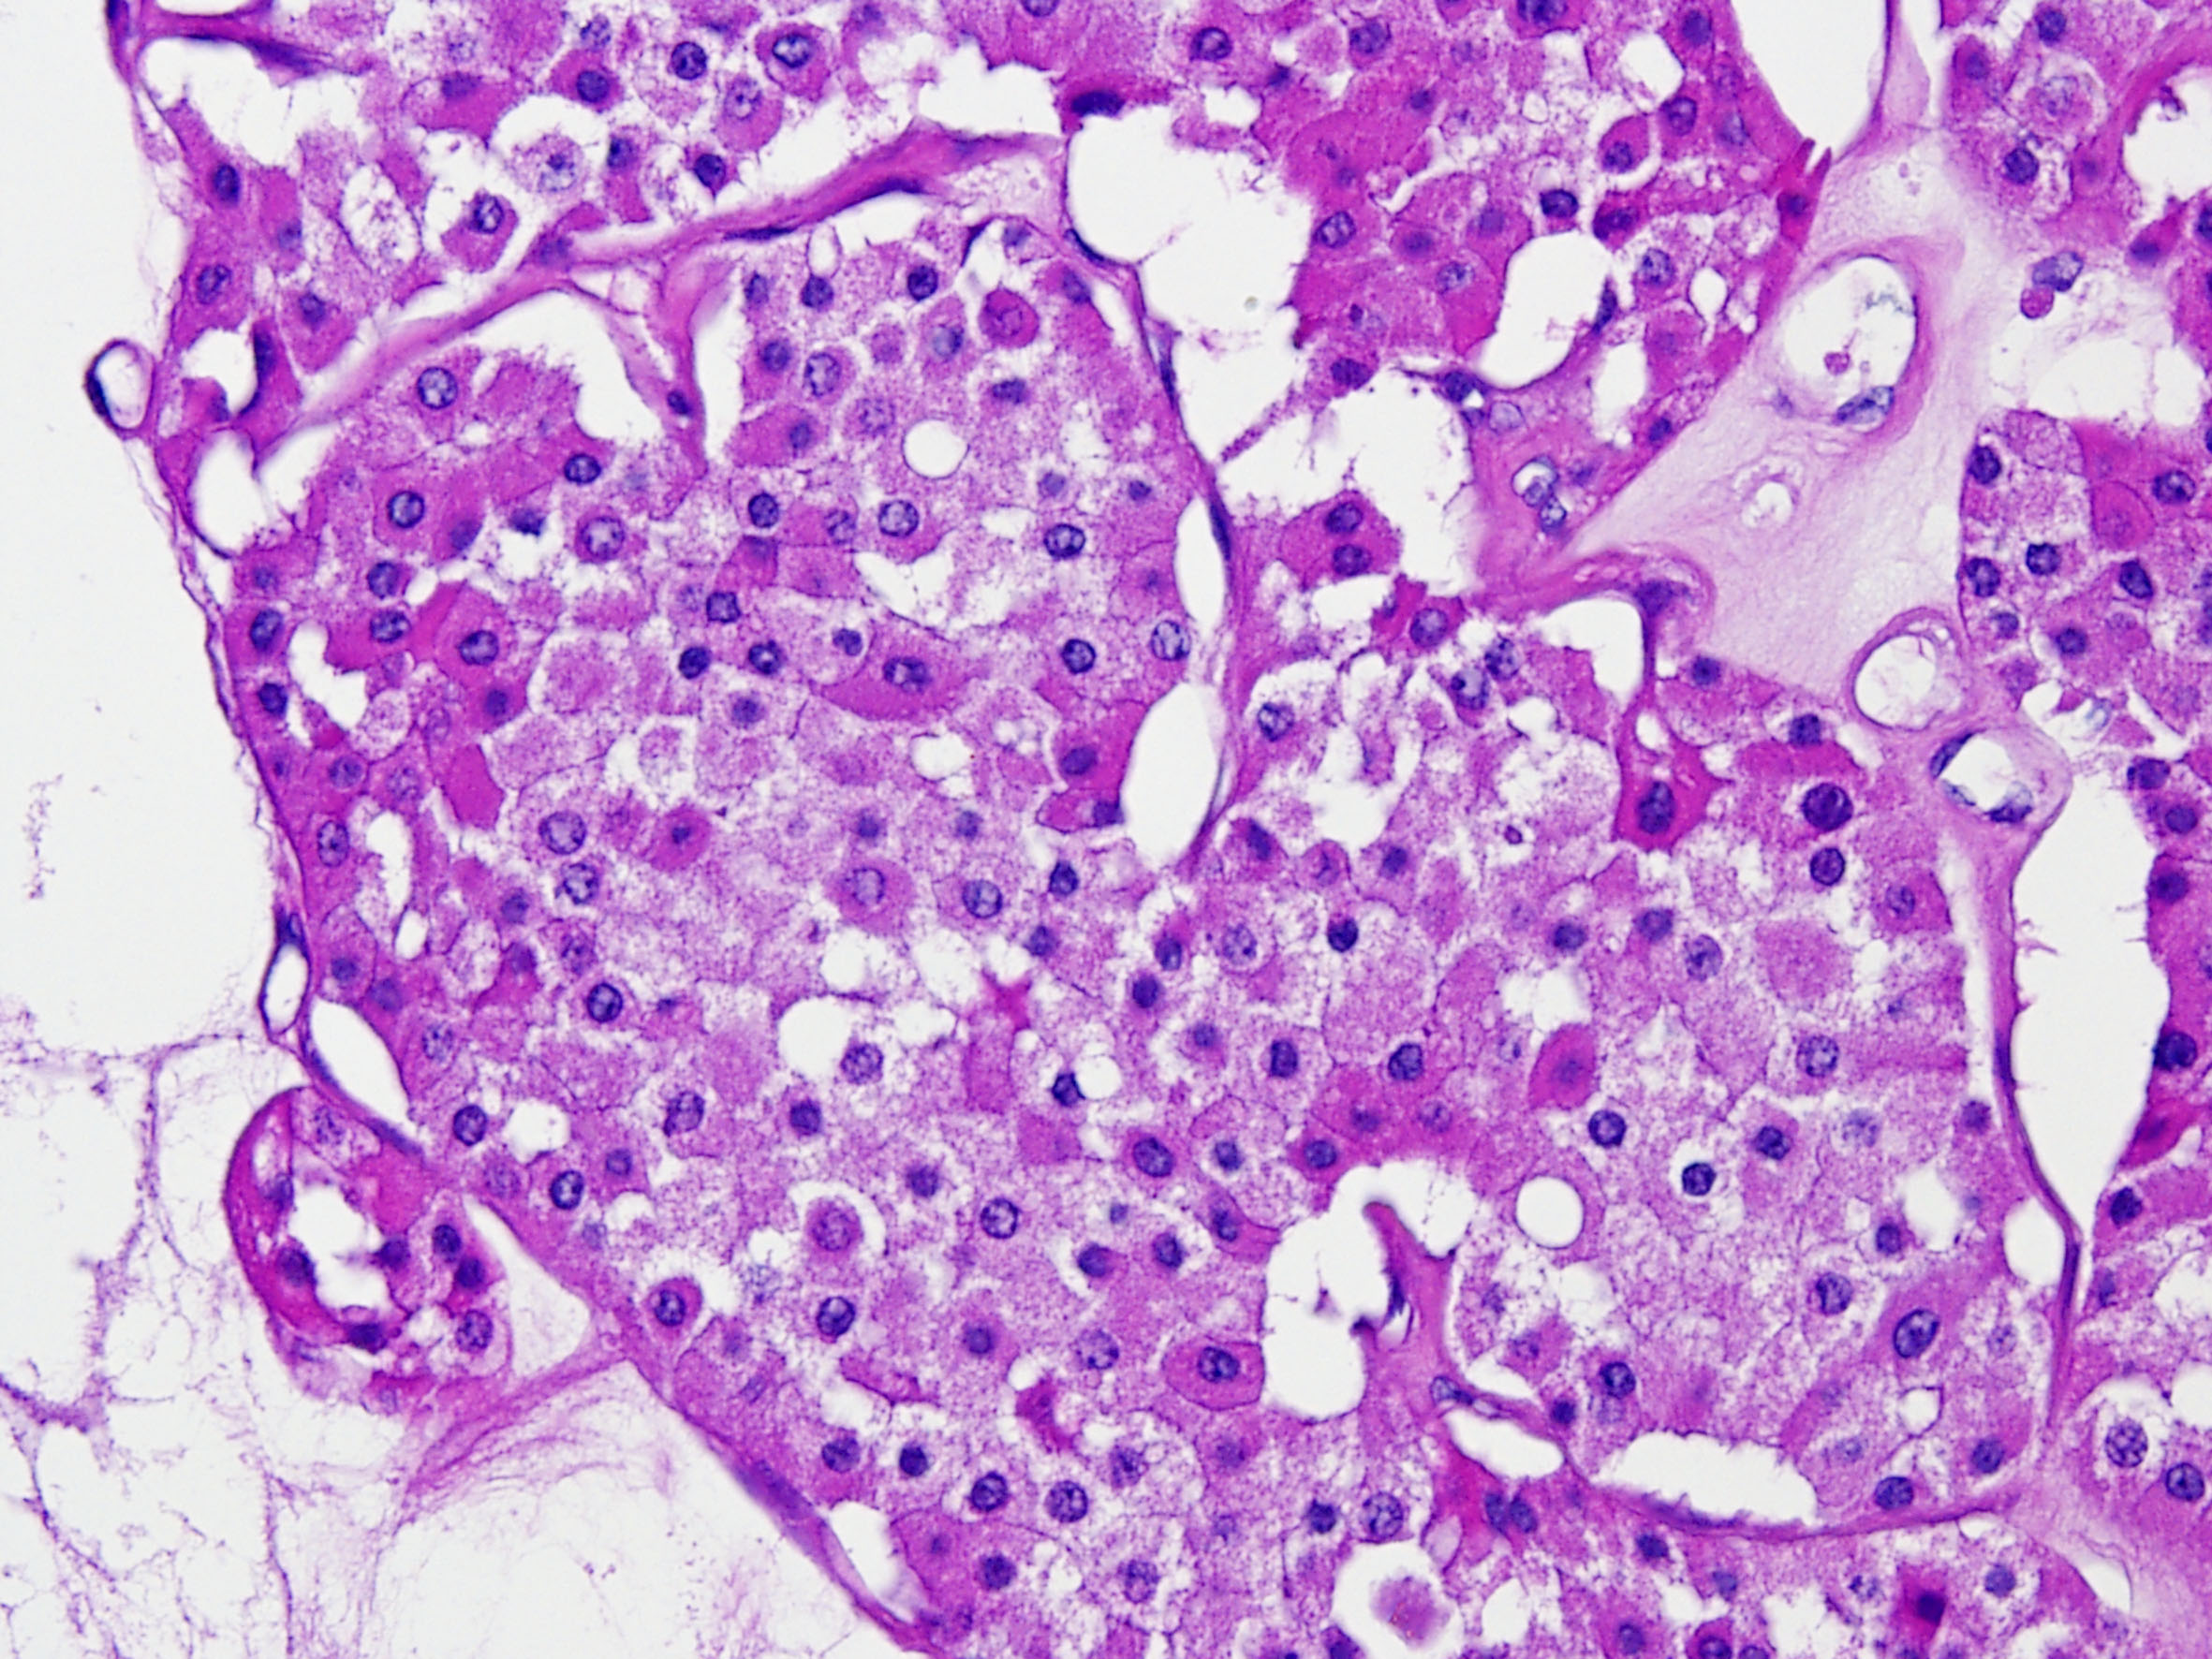

Renal tumor grading

Case ID: 290

WHO/ISUP grade 1

WHO/ISUP grade 2

WHO/ISUP grade 3

WHO/ISUP grade 4